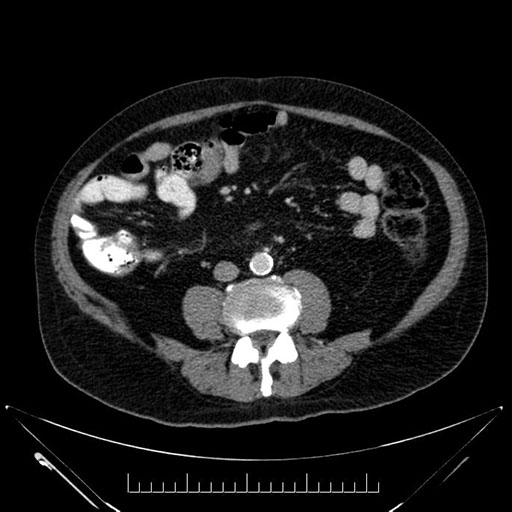

Whipple (pancreaticoduodenectomy) [case 7]

Imaging Analysis

Look through the patient's CT scan to identify any areas of concern for the necessary procedure.

Axial - stented